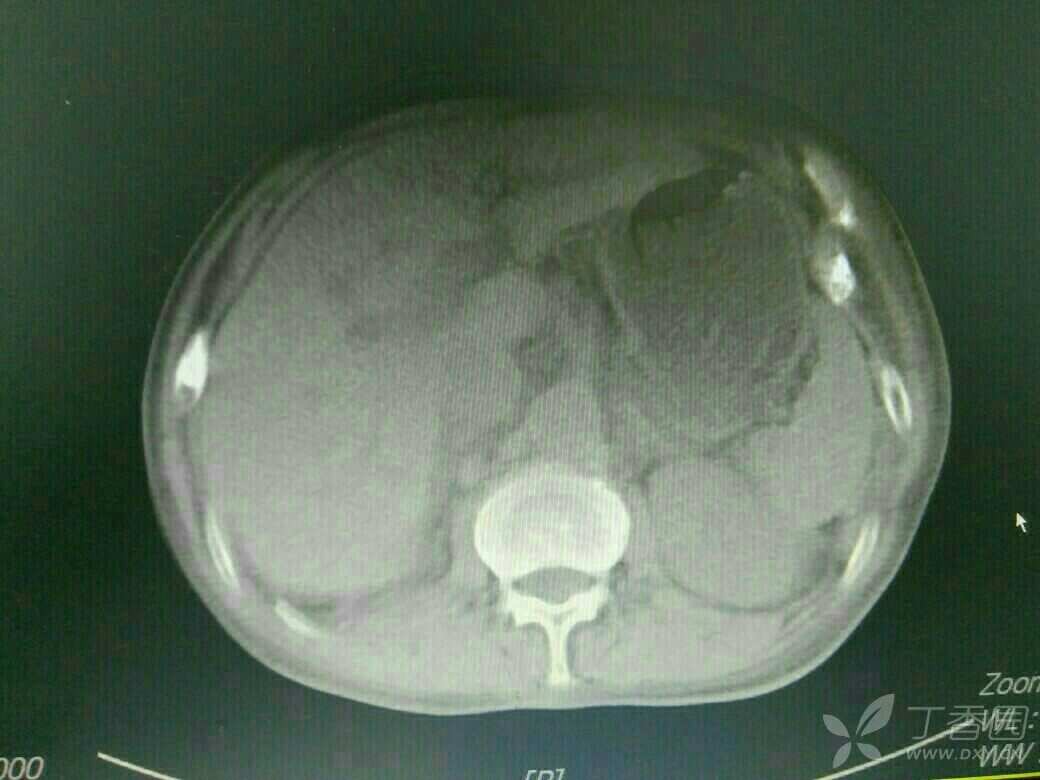

患者71岁老年男性,既往copd,多次住院治疗,平时状态好的时候气促也明显,这次是受凉在当地输液10多天,病情加重入院,来的时候诉乏力气促,上腹胀痛,不能进食,双下肢中度水肿,颈静脉怒张,肝功提示转氨酶400多,bnp6000多,心电图是快速房颤,心脏彩超示EF26%,CT示双侧胸腔积液,肝周积液,门静脉增宽,直径1.8cm,与强心利尿后,来的时候血气还可以,现在血气是呼酸合并代碱